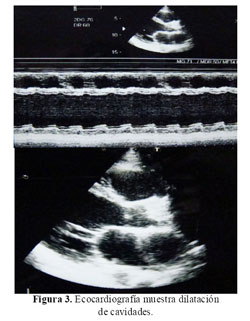

La Rx del tórax mostró cardiomegalia masiva y congestión pulmonar (Figura 1). En la tomografía cerebral se evidenció una hipodensidad en áreas frontales y parietales derechas a nivel cortical y subcortical con transformación hemorrágica (Figura 2). La ecocardiografia era muy similar a la previa, con dilatación e hipocinesia global y fracción de eyección de 25% (Figura 3).

En el caso, la paciente sufrió el accidente cerebro vascular (ACV) a las 12 semanas después del parto. El ACV clínicamente comprometía todo el hemicuerpo izquierdo con un plejia densa y de inicio súbito (Figura 2). La incidencia descrita de ACV en mujeres no gestantes de 15 a 44 años es de 10,7 por 100 000 mujeres (11), mientras la incidencia en el embarazo es de 4,3–210 por 100 000 partos (12). Por el tiempo descrito desde el inicio de la enfermedad actual, se alejarían causas como trombosis venosa cerebral y angiopatía cerebral postparto (11). Debemos tener en cuenta que nuestra paciente desarrolló el ACV pasado el tiempo establecido para el puerperio inclusive.